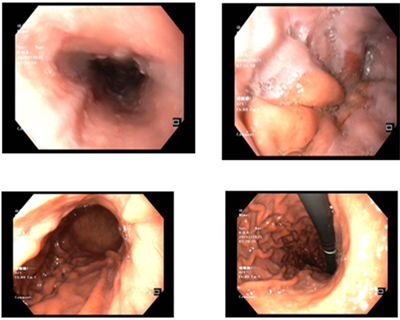

UNG THƯ DẠ DÀY KHỞI PHÁT SỚM

Theo Globocan 2022, ung thư dạ dày đứng thứ 5 về tỷ lệ mắc và tỷ lệ tử vong, với 968 784 ca mắc mới và 660 175 ca tử vong. Bệnh tiến triển thầm lặng, các triệu chứng ban đầu  thường mơ hồ và không đặc hiệu dễ nhầm lẫn với các bệnh lành...